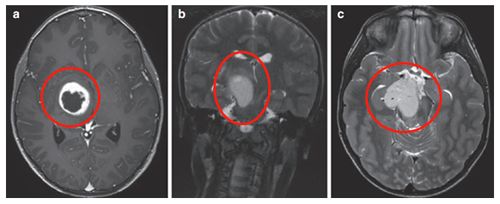

9岁患儿小石体表存在多发咖啡斑,随年龄增长斑点数量呈现增加趋势。除皮肤表现外,患儿腋窝区域出现雀斑样改变,家长决定进行医学检查。影像学检查发现右侧丘脑存在低级别胶质瘤,病变累及颞叶区域。

临床治疗案例分享前文提及的小石经鲁特卡教授治疗后病情稳定。患儿因左面部、四肢出现3周急性症状,伴持续3个月以上的轻微口齿不清就诊。体表存在多发性咖啡斑及腋窝雀斑,MRI显示右侧丘脑环形强化结节状肿瘤,累及内侧颞叶结构。

鲁特卡教授实施经颞中回-脑室入路次全切除术,病理证实为WHO I级毛细胞星形细胞瘤,BRAF重复融合、BRAF V600E及H3K27M检测均为阴性,基因检测检出NF1基因变异。术后影像学随访显示丘脑部分切除及中脑残留病灶,制定个体化辅助放疗方案,患儿治疗反应良好。术后6个月复查确认肿瘤控制稳定。